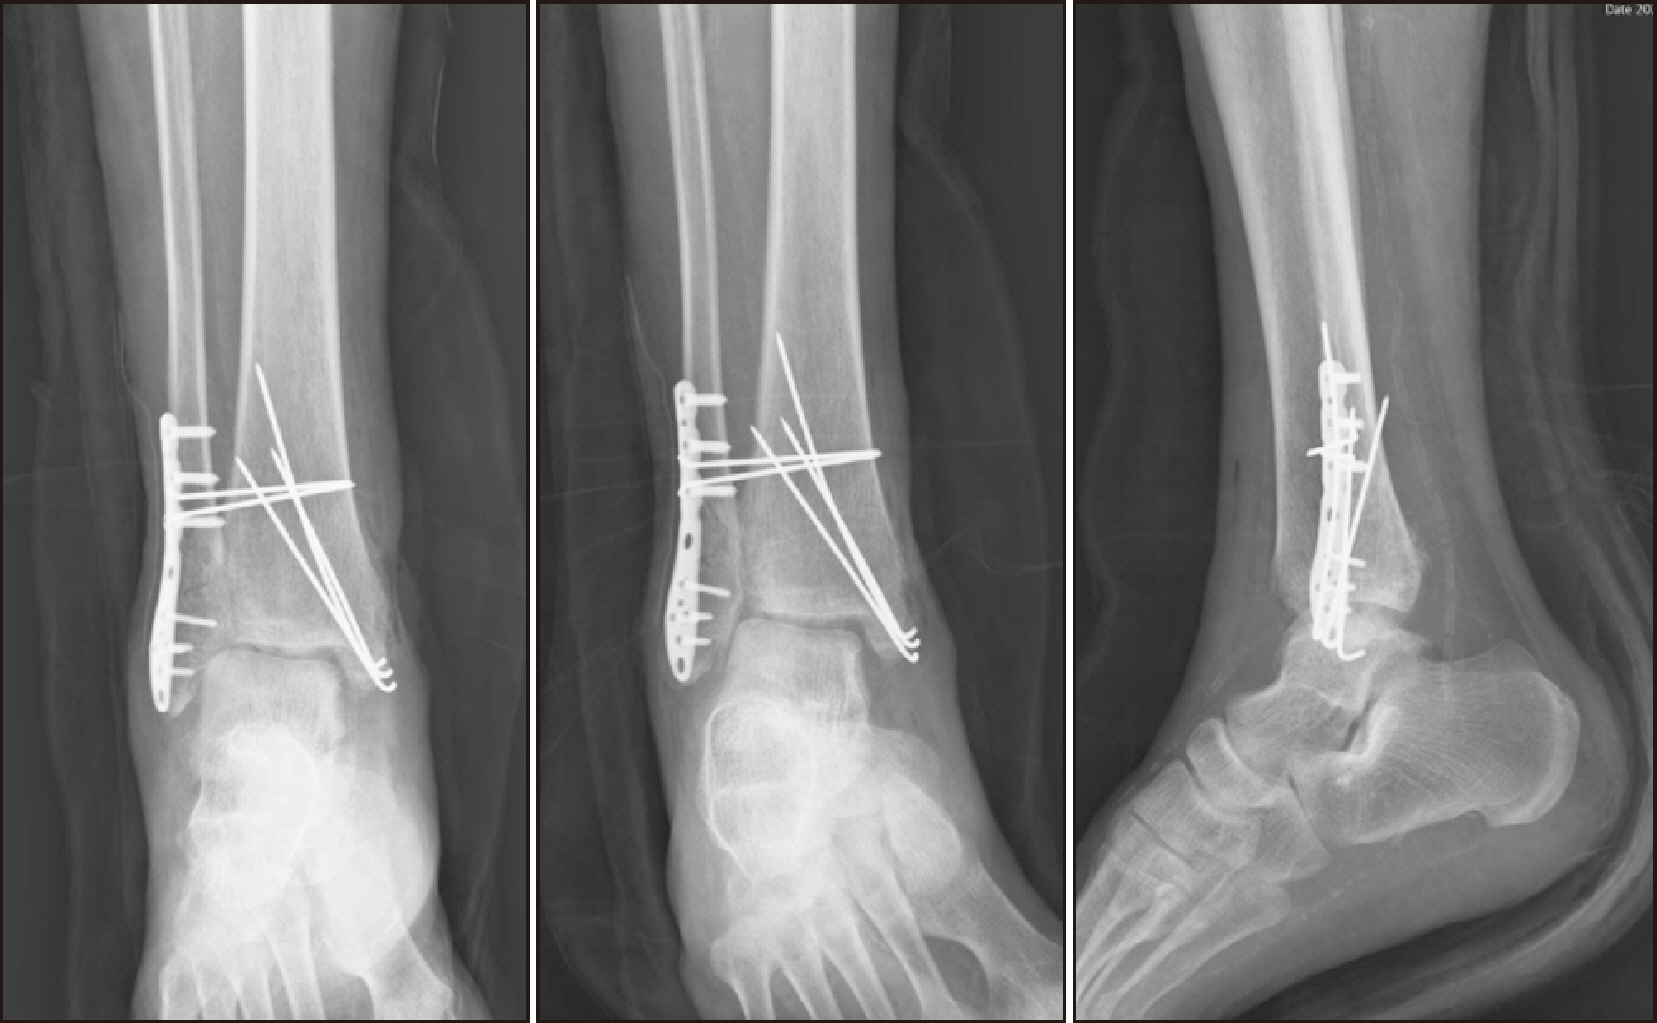

Charcot neuroarthropathy (CN), also known as Charcot arthropathy, is a complex, progressive disorder primarily affecting the foot and ankle. This case report describes a multifaceted management strategy for a 54-year-old male with diabetes mellitus, end-stage renal disease, and presumed underlying Charcot arthropathy who experienced a traumatic ankle fracture. The initial surgical plans were delayed because of systemic infection indicators, including elevated C-reactive protein levels and high fever. The patient underwent multiple surgical interventions and faced challenges, including metal failure, implant-associated infection, and tibiotalar joint dislocation. A multidisciplinary approach involving orthopedic surgeons, nephrologists, and endocrinologists was crucial for managing the case effectively. In particular, the patient declined a below-knee amputation and opted for comprehensive surgical intervention, resulting in improved functionality at the latest follow-up. This case highlights the complexities of managing CN in patients with multiple comorbidities and emphasizes the need for a nuanced, patient-centered approach.